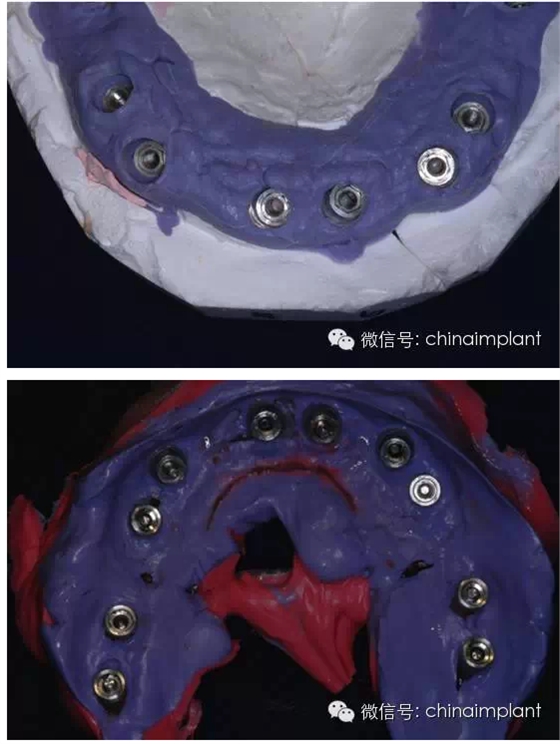

此案例為術(shù)后兩周戴臨時(shí)牙。過去因?yàn)閾?dān)心感染的問題,一個(gè)月以內(nèi)帶臨時(shí)牙也叫做即刻負(fù)重或者早期負(fù)重。(現(xiàn)在當(dāng)天戴臨時(shí)牙(即刻復(fù)重)的情況也非常常見).

本案例已經(jīng)將近10年了(2005年12月),但是修復(fù)效果個(gè)人認(rèn)為很不錯(cuò),所以拿出來和大家分享。